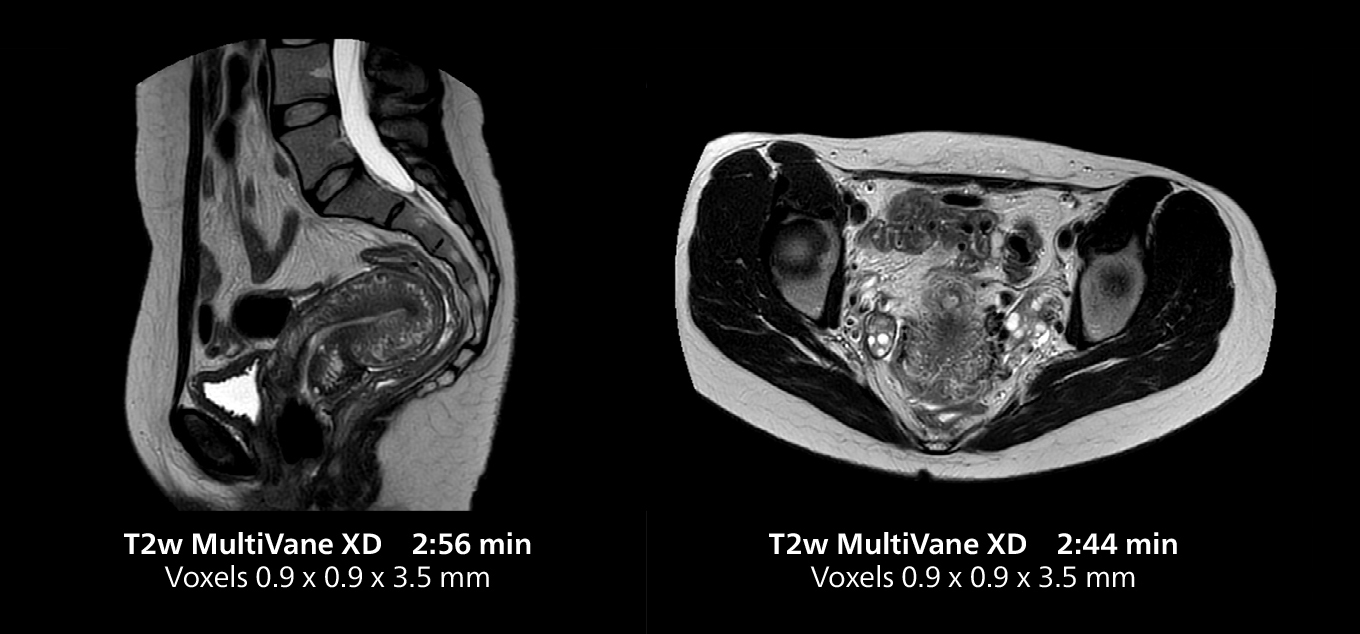

Female pelvis imaging

This MRI case illustrates good resolution and imaging quality obtained within reasonable scan times using the MR 5300 1.5T system with the anterior torso cardiac coil that allows use of a large field of view (FOV).

Female pelvis imaging

This MRI case illustrates good resolution and imaging quality obtained within reasonable scan times using the MR 5300 1.5T system with the anterior torso cardiac coil that allows use of a large field of view (FOV).